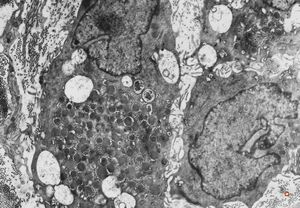

M,40y. | granular cell tumor

F,30y. | granular cell tumor